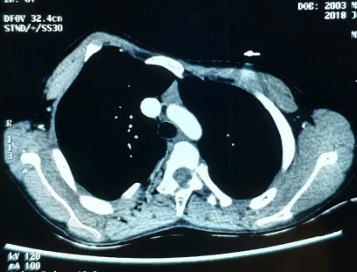

入院查体:右侧颈部有陈旧性手术疤痕,右侧胸锁关节突起,右侧前胸壁突起,伴胸骨附近凹陷。术前CT检查:右侧前胸壁明显突起,左右胸廓不对称。其他检查未发现手术禁忌。

图3,右侧上胸壁严重突起,左右胸廓不对称。

图4,右侧胸壁突起。